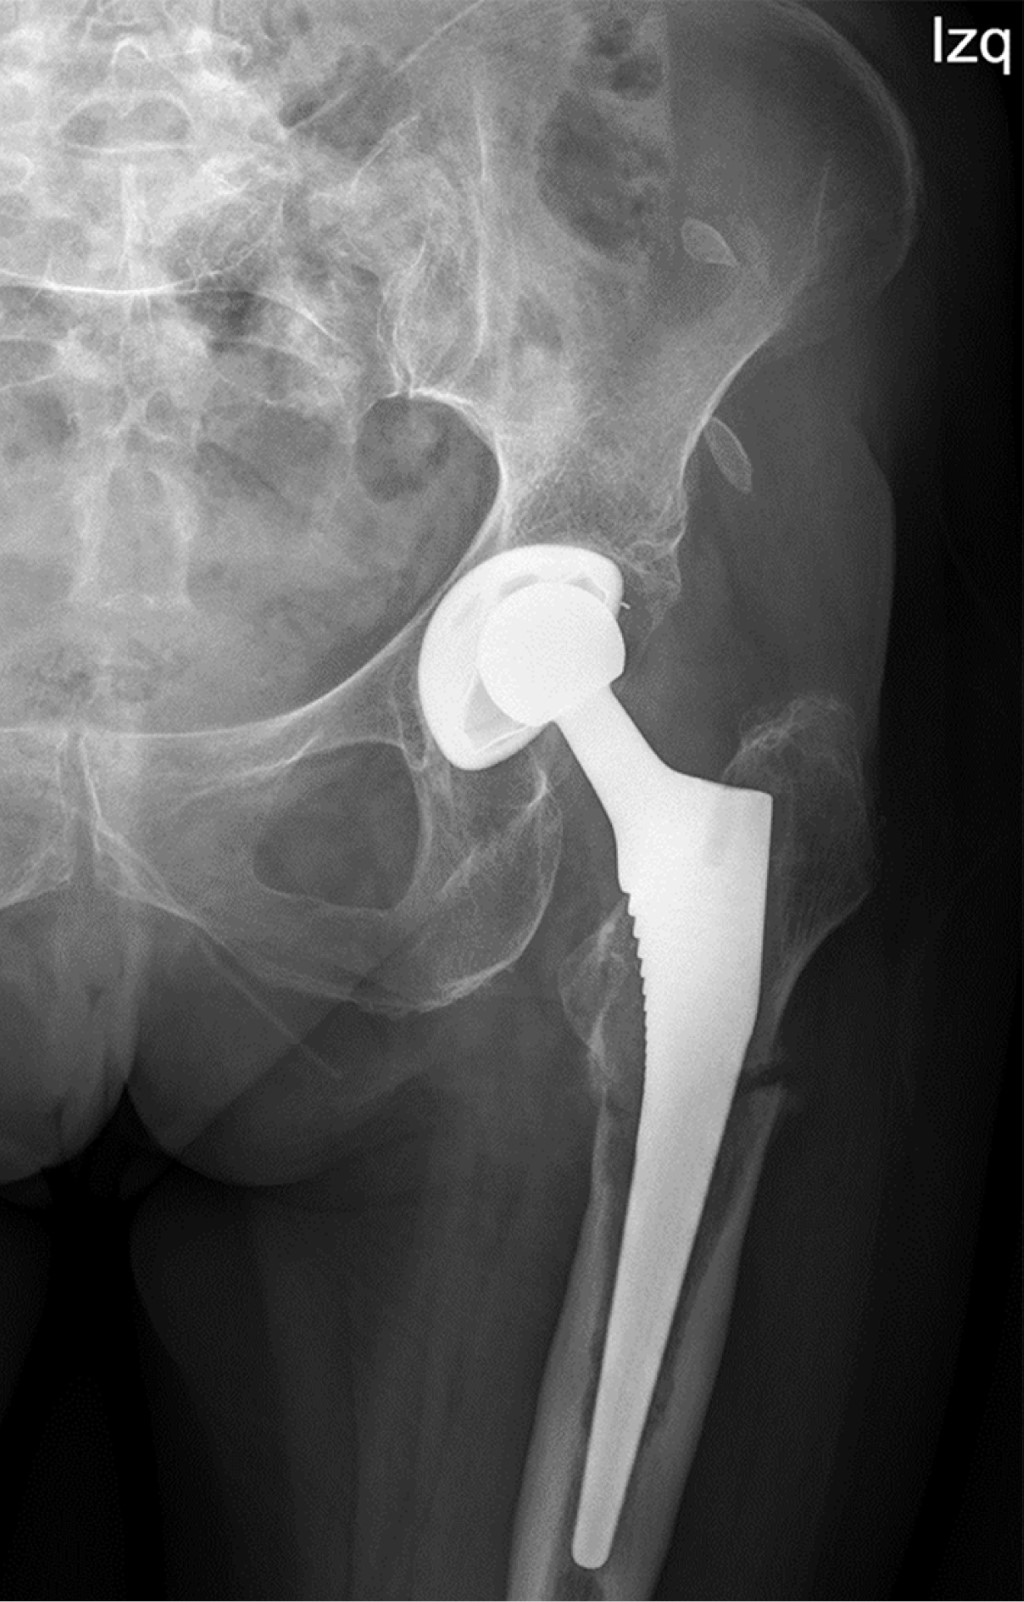

Minimizing risk: evaluation of the relationship between femoral stem loosening and the risk of presenting with peri-prosthetic hip fracture

Introduction: evaluation of predictors of periprosthetic fracture in loosened femoral stems. Material and methods: retrospective case-control study comparing aseptic loosened stems in two groups: cases: patients who experienced periprosthetic femoral fracture before replacement could be performed (n = 9). Controls: experienced prosthetic replacement without fracture (n = 19). Results: pain intensity (VAS) was the most important aspect (p = 0.01), predominating in the controls. The simple radiological parameters did not show statistically significant findings predictive of peri-prosthetic fracture (number of Gruen zones, sum of them in mm, stress shielding, pedestal, polyethylene wear, stem subsidence). The role of complementary tests (CT and scintigraphy) for the definitive diagnosis of loosening was relevant, but not significant. The type of implant showed no differences. Overall implant survival was higher in cases than in controls (p = 0.016). This difference continues when comparing each loosened stem until fracture or replacement (p = 0.024). Conclusion: the main factor protecting against fracture is the replacement of a stem with clinical and radiological diagnosis of loosening. Adequate follow-up of the patient plays a determining role in this, especially when considering the greater intensity of pain in the controls, which used to guide surgeons to perform replacements before the fracture occurred. This is reinforced if we take into account that up to one third of the cases did not have regular check-ups, and therefore did not have the opportunity for replacement prior to the fracture. The role of complementary tests (CT and scintigraphy) is also very important, taking into account the low diagnostic yield obtained from simple X-rays.

Figure 1